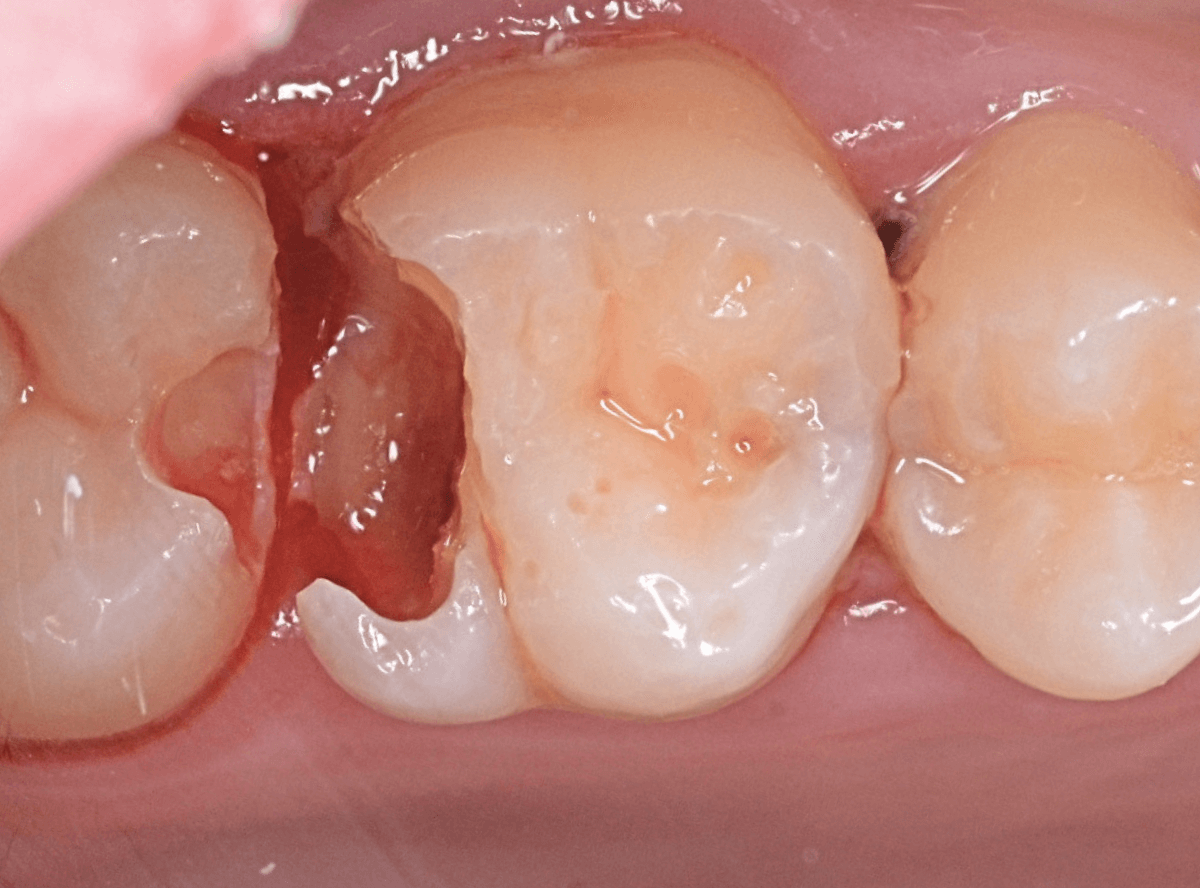

Case.23 歯のすきまから両側が大きな虫歯

「下の奥歯が痛む」という訴えで来院された患者さんのケースです。

目視でも、手前の奥歯がかけていて、中で虫歯が広がってるであろうことは予想できます。

ピンセットで歯を叩いてみても、手前の奥歯が痛むようです。

レントゲン写真で確認します。

青い線が神経、赤い線が虫歯の範囲です。

奥歯の方がより深い虫歯に見えますが、再度打診で確認したところ、やはり手前の奥歯が痛むそうです。

状況から、まず手前の奥歯から治療となりました。

麻酔をして、手前の奥歯のレジンを慎重に外します。

前に虫歯の治療をした時点で、神経スレスレの状態でしたので、削りすぎないように慎重にレジンを外さなければいけません。

レジンを外して、う蝕検知液で確認します。

レジンの中で虫歯が進行していたのがわかります。

慎重に全ての虫歯を除去しました。

何とか、神経が露出せずに済んでいます。

お薬をつめて、セメントで蓋をして経過観察します。

後日、状況を確認したところ、虫歯処置した後も、手前の奥歯が痛むとの事でした。

「我慢できないほどでもない」との事でしたので、引き続き経過観察しつつ、奥歯の治療を治療する事になりました。

奥歯は、レントゲンで見た通り、少し歯を削るとすぐに虫歯の穴が出てきました。

こちらは、ある程度虫歯を取ったところで染め出してみると真っ赤です。

ですが、何とか神経に達する前に、全ての虫歯を除去できました。

神経の治療が必要かと思っていたので、その点は幸運でした。

奥歯もお薬をつめて、セメントで蓋をして経過観察です。

何とか神経を取らずに済ませたいですが、どうなる事か・・・。